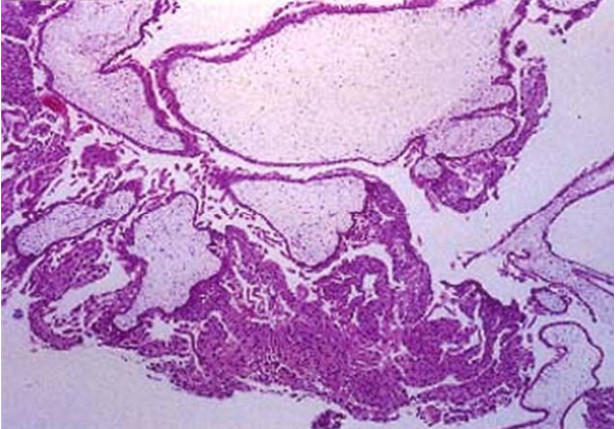

97 一位 30 歲女性因陰道出血就醫。她上次月經是三個月前,但因工作忙碌並未接受任何檢查。此次身 體檢查發現她的子宮較大,且子宮腔有如雪花般的內容物存在,但並未發現有胎兒存在。她接受子 宮內膜刮除術。圖示是刮除標本的顯微鏡下變化。她最可能的診斷為何?

(A) 絨毛膜癌(choriocarcinoma) (B)子宮內膜癌(endometrial cancer) (C)水泡狀胎塊(hydatidiform mole) (D)不完全流產(incomplete abortion)